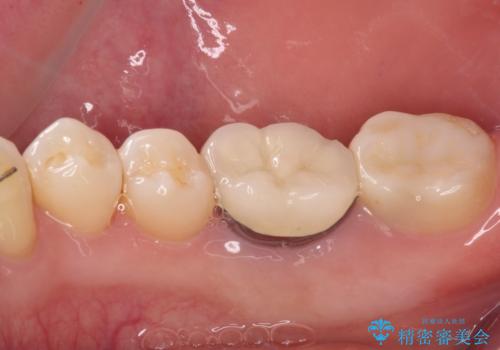

精度の高いセラミックインレーによる修復治療を行うこととしました。

セラミックインレー装着後はフロスの引っかかるストレスから解放され、患者様には大変満足していただきました。